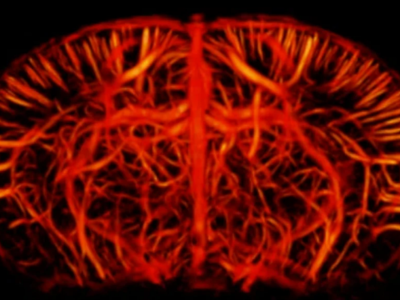

No 17 | Les vaisseaux du souvenir